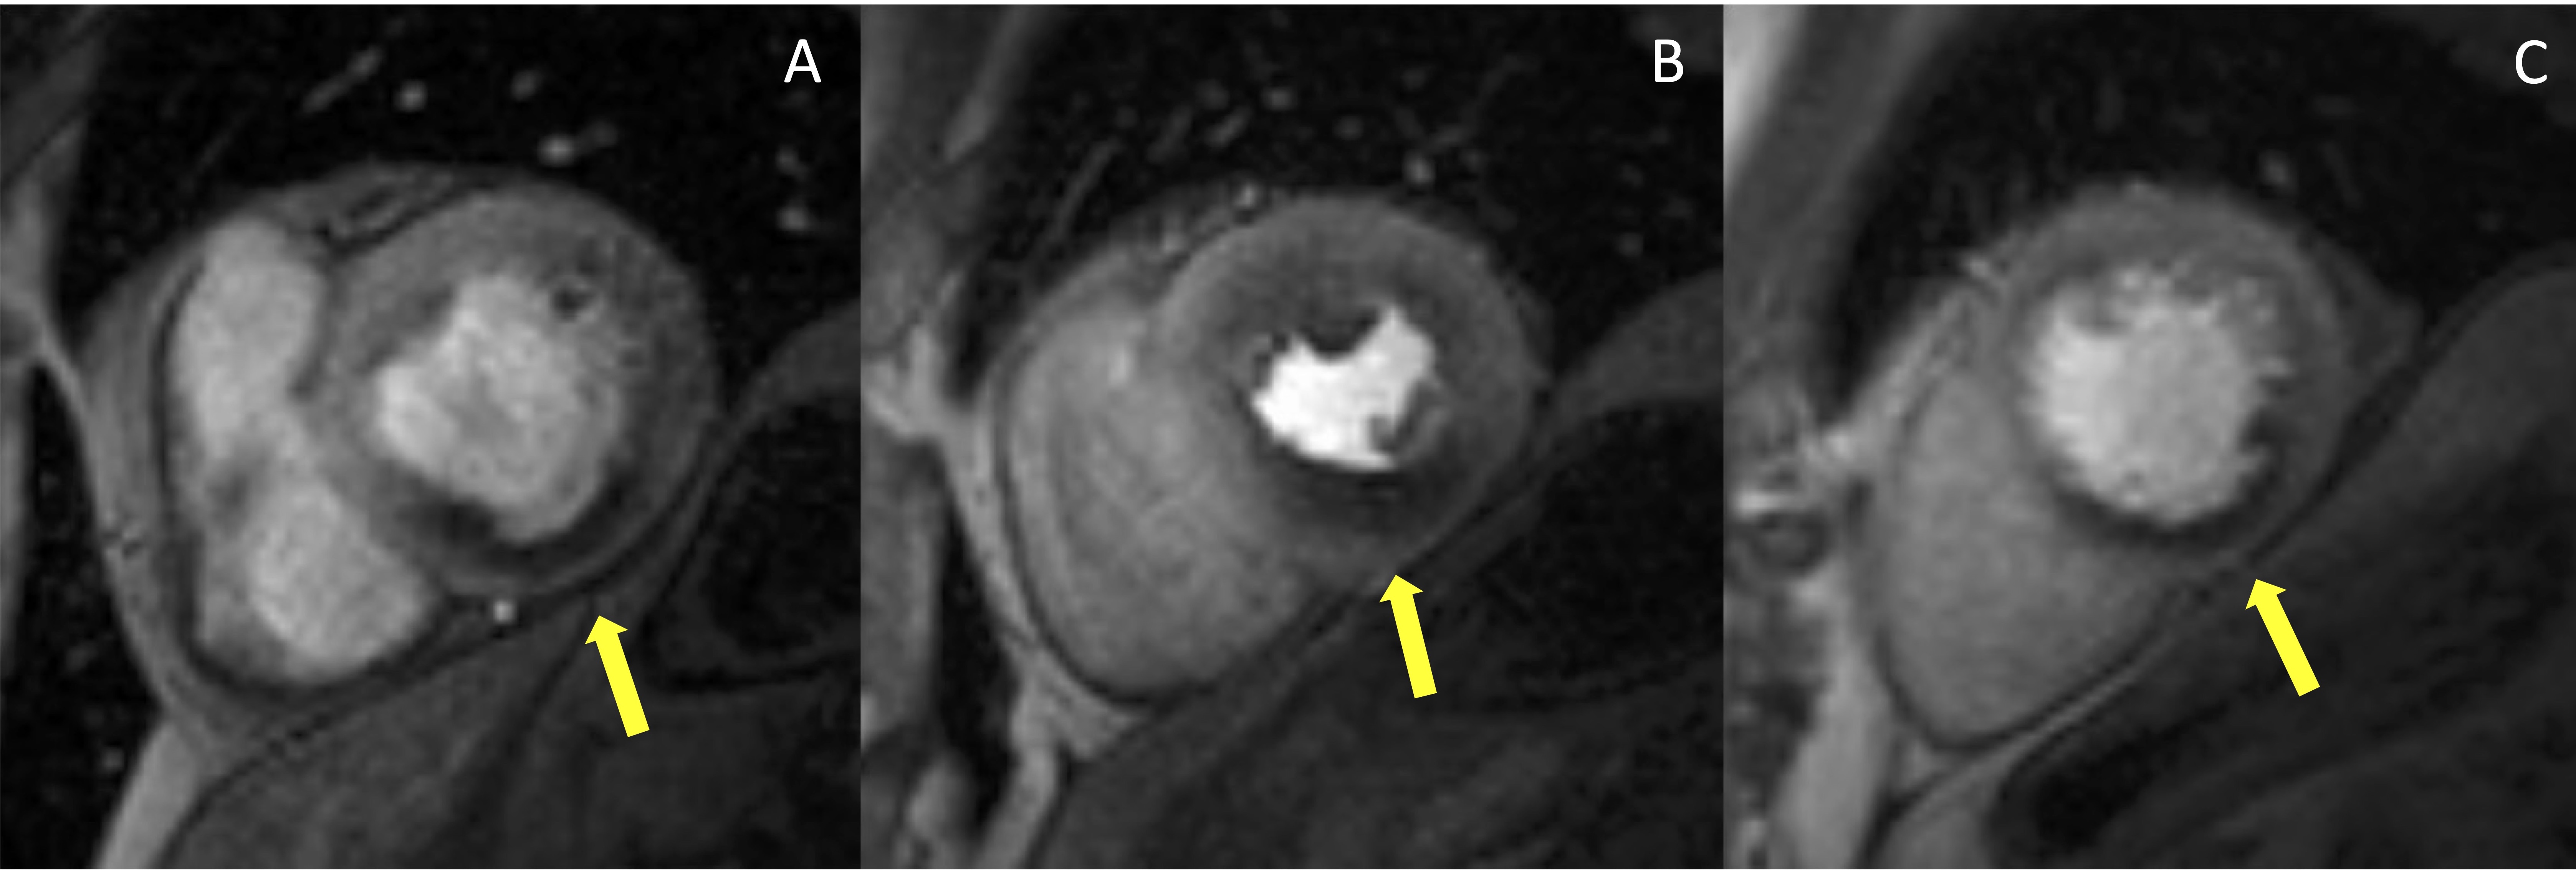

The perfusion images are analyzed using the American Heart Association (AHA) 16-segment model [29]. By assessing the number of segments with perfusion defects due to ischemia, the global ischemic burden can be estimated. The perfusion defect is usually most evident about three heart beats after the maximal contrast enhancement of the ventricular cavity and continues while the contrast washes out. It is important to distinguish inducible perfusion defects from artifacts. The most common is the ‘dark-rim artifact’, which appears as a hypointense area in the subendocardial layer of the myocardium, usually due to low spatial and temporal resolution (Fig. 3). Dark rim artifacts usually appear as the gadolinium first reaches the ventricular cavity, but it vanishes once the myocardium is enhanced. Moreover, they are present during both rest and stress conditions in the absence of underlying scars in the LGE images.

Fig. 3.Example of stress CMR images showing the ‘dark-rim artifact’. CMR adenosine-stress perfusion in a 44-year-old man with a known congenital coronary artery abnormality (RCA with a high take off and inter-arterial course). Short axis rest and stress perfusion images are shown respectively at the basal (A,D), mid-ventricular (B,E), and apical (C,F) levels. There is evidence of a transient hypointense area in the subendocardial layer of the mid-ventricular septal segments (yellow arrows) both in the rest and stress images (B,E), during the early phase of passage of GBCA bolus through the left ventricle, suggestive for “dark rim artifact”. Corresponding LGE images (G,H,I) show no myocardial scars. CMR, cardiovascular magnetic resonance; LGE, late gadolinium enhancement; RCA, right coronary artery; GBCA, gadolinium-based contrast agent.